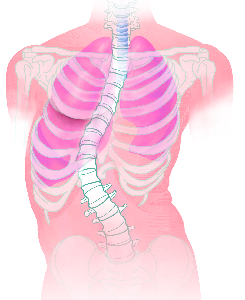

Detailreiche Fotografien aus der medizinischen Praxis ergänzen die Texte; moderne, genaue,

wissenschaftliche Zeichnungen geben Einblick in die Anatomie und die Funktion der Lunge und

anderer Organe.